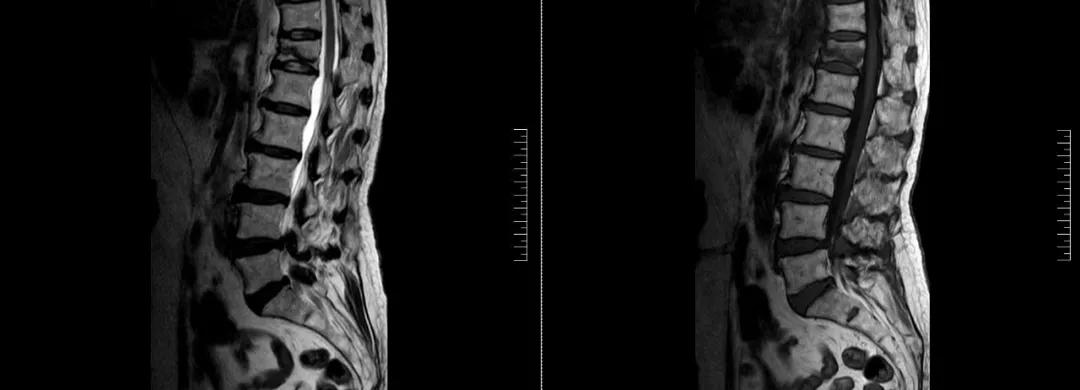

術前磁共振檢查提示腰1椎體新鮮壓縮性骨折

術后復查CT可見骨水泥彌散充分